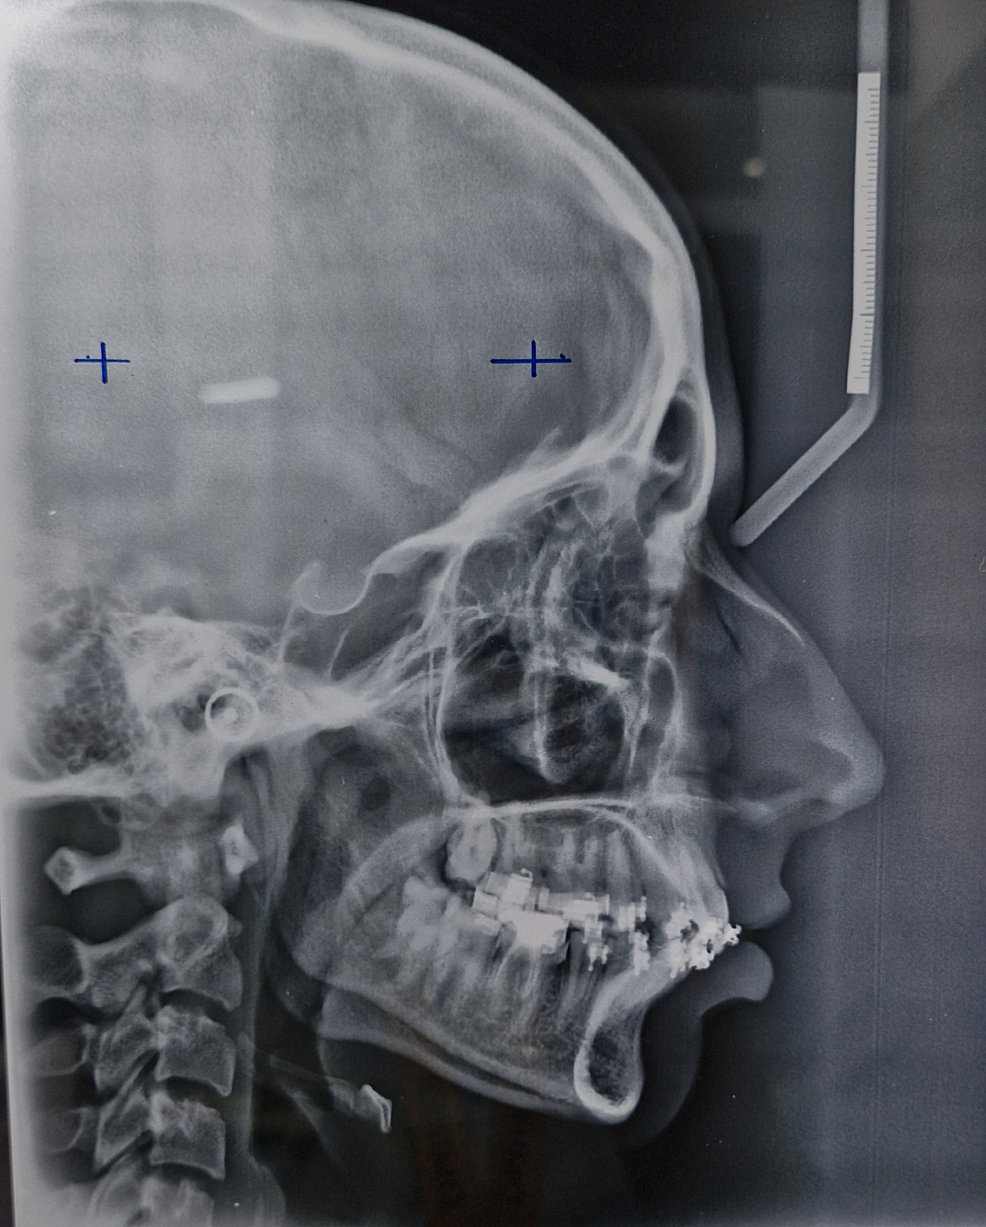

Figure 1 from Retraction of Anterior Teeth with Temporary Anchorage Retraction Of Anterior Teeth They have gained popularity among orthodontists for en masse retraction of anterior teeth after first premolar extraction in maximum anchorage. Anchorage devices also known as tads is anterior teeth retraction, most commonly needed in bimaxillary protrusion cases or class ii. Molar distalization has been a validated method to correct dental sagittal relationships and create space to relieve mild. The clinical. Retraction Of Anterior Teeth.